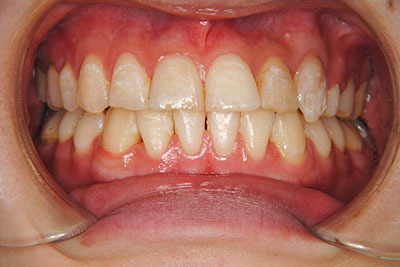

⑧リスクと副作用:マルチブラケット装置(T21ブラケット)を初めてつけてから3,4日、食事の時に歯が少し痛かったとのことでした。治療後のエックス線写真で、歯根吸収はほとんど観察されませんでしたが、歯肉を診ると残念ながら下の真ん中の前歯2本の間に若干の歯肉退縮(ブラックトライアングル)が生じていました。

マルチブラケット装置(T21ブラケット)に加えて口の中のゴムをたいへん頑張って使っていただいた結果、治療前の予想期間1年から1年半であったところ、10カ月で動的治療を終了できました。上下真ん中のズレも治りぴったりになりました。 これからは歯並びの維持安定のためリテーナー(保定装置)を使いながら定期健診となります。